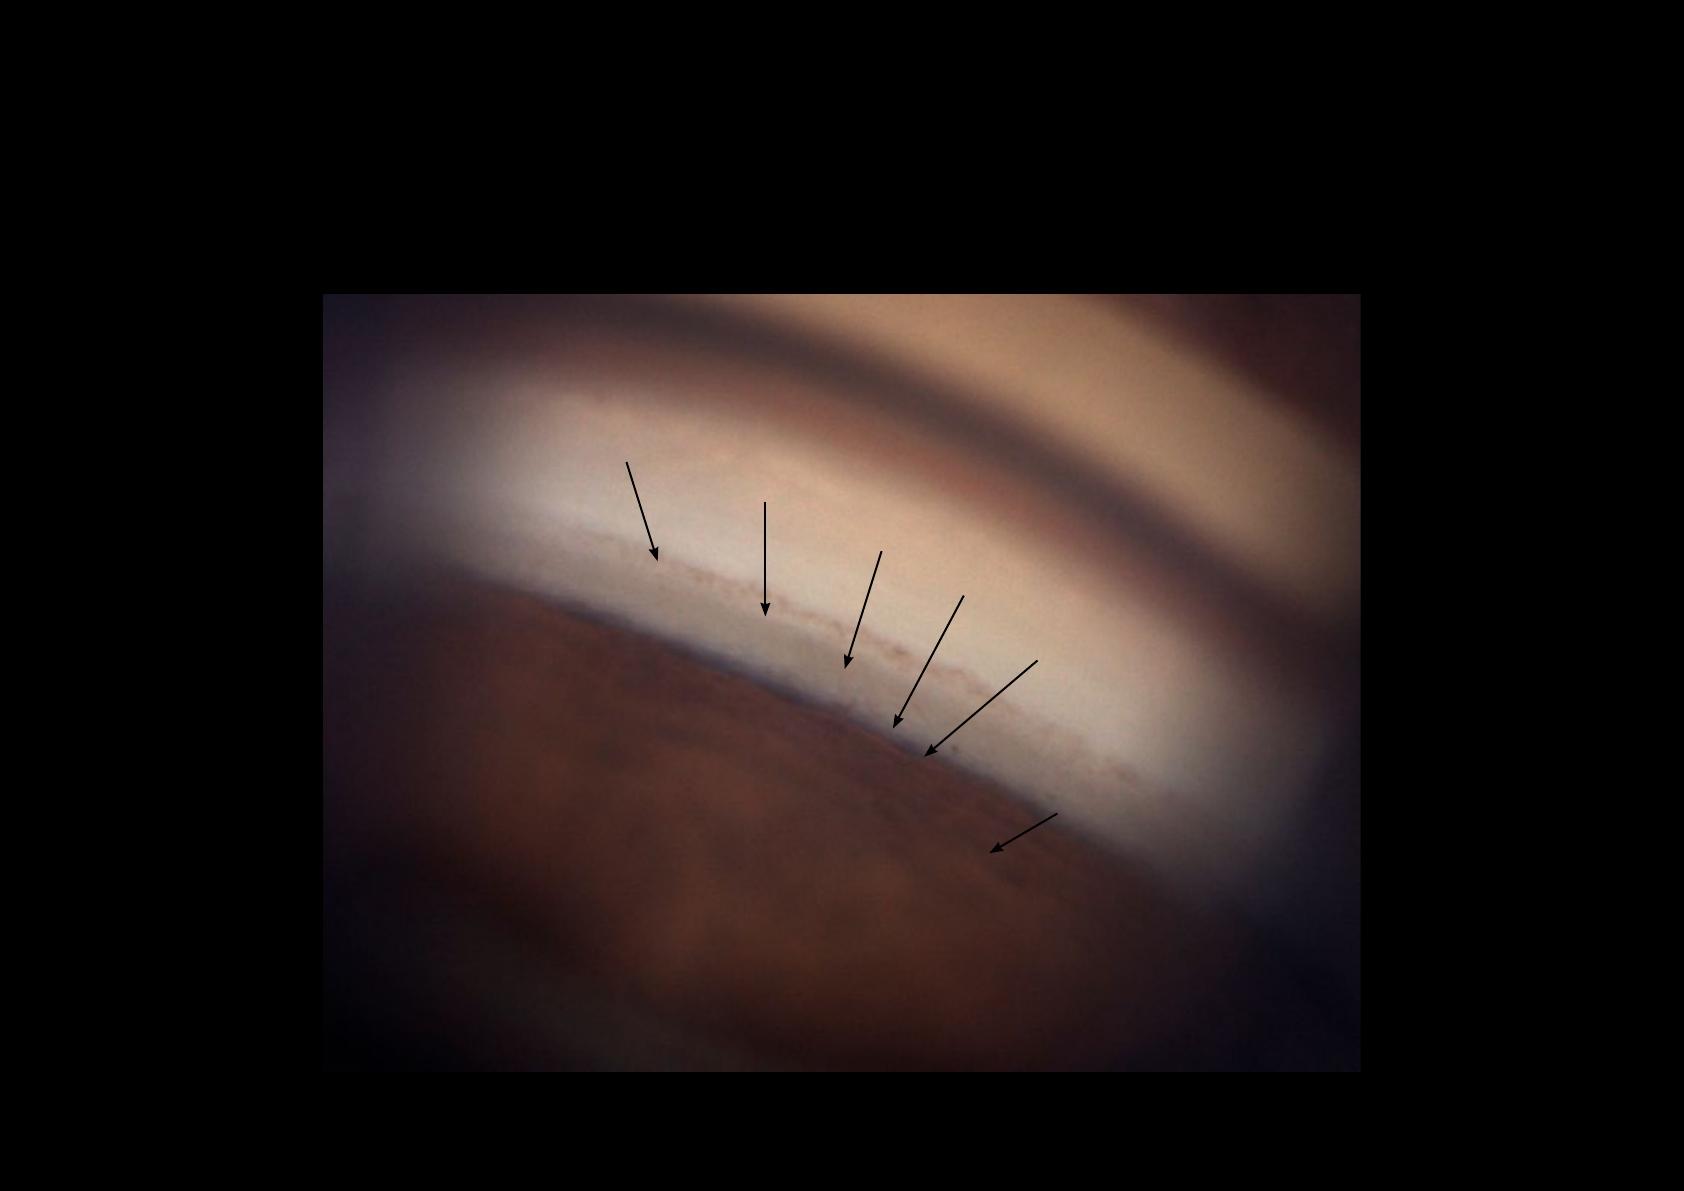

Glaucome chronique par fermeture de l’angle

Avec l’aimable autorisation du Professeur Jean-Paul Renard, Paris

Zones d’adhérence de l’iris au niveau du trabéculum. Elles sont

à l’origine d’une fermeture progressive de l’angle. Elles risquent de

perturber la fonctionnalité de l’angle irido-cornéen.

SYNÉCHIES ANTÉRIEURES